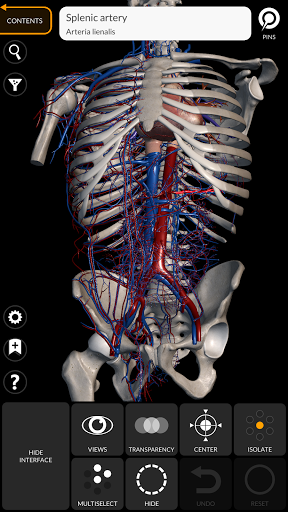

يتيح لك "Anatomy 3D Atlas" دراسة التشريح البشري بطريقة سهلة وتفاعلية.

من خلال واجهة بسيطة وبديهية، من الممكن ملاحظة كل بنية تشريحية من أي زاوية.

تتميز النماذج التشريحية ثلاثية الأبعاد بتفاصيل خاصة ودقة تصل إلى 4K.

يسهل التقسيم حسب المناطق والمناظر المحددة مسبقًا مراقبة ودراسة الأجزاء الفردية أو مجموعات الأنظمة والعلاقات بين الأعضاء المختلفة.

• الجهاز القلبي الوعائي

• من خلال تحديد نموذج أو دبوس، يظهر المصطلح التشريحي ذي الصلة